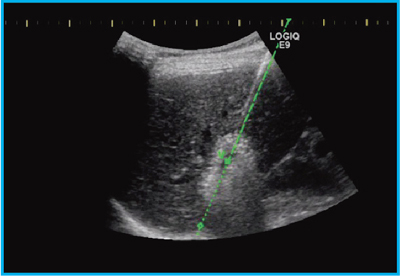

図3は,UltraProeを用いたIn-Plane Needle Trackingによる肝生検だが,Needle Trackingによって適切な位置に穿刺できたかを確認し,eTRAXを抜去後,内筒を生検針に替えて生検を行った。

図3 UltraProeを用いたIn-Plane Needle Trackingによる肝生検